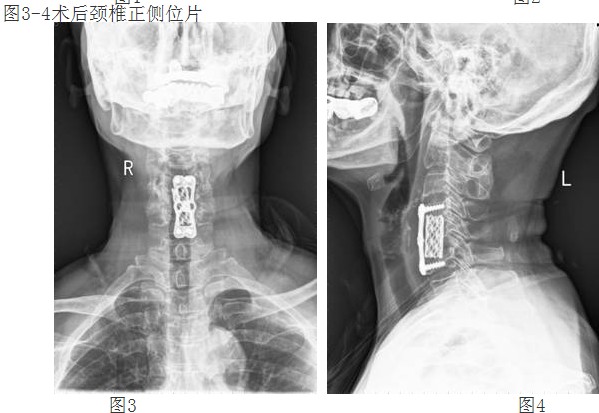

經(jīng)過譚主任和全科醫(yī)護(hù)人員充分的術(shù)前準(zhǔn)備和討論,對(duì)患者實(shí)施了頸椎前路頸4/5、頸5/6椎間盤摘除、頸5椎體次全切除、椎管減壓鈦網(wǎng)植骨融合、頸前路鈦板固定術(shù)。手術(shù)取得了成功。術(shù)后第二天,李阿婆的四肢麻木就明顯減輕,握手能力和手臂力量都明顯好轉(zhuǎn)。

譚主任介紹,重度頸椎病手術(shù)治療難度大風(fēng)險(xiǎn)高,一旦脊髓神經(jīng)和骨質(zhì)鈣化韌帶相粘連,手術(shù)用力稍有不當(dāng),就會(huì)損及脊髓而造成終身癱瘓。脊柱外科成立以來,頸椎前后路手術(shù)已陸續(xù)開展,三年前在廣東省中醫(yī)院和中山醫(yī)一、二院教授指導(dǎo)下完成,2011年我科已經(jīng)成功獨(dú)立完成了多例頸椎病手術(shù),現(xiàn)在我科在該技術(shù)已趨向成熟,頸椎前路手術(shù)是目前治療脊髓型頸椎病可靠而有效的方法之一,它具有直視下減壓徹底、出血少、創(chuàng)傷小等優(yōu)點(diǎn),有利于術(shù)后脊髓神經(jīng)的恢復(fù)。

經(jīng)頸前路減壓植骨融合內(nèi)固定術(shù)屬復(fù)雜高難度高風(fēng)險(xiǎn)手術(shù),該技術(shù)的成功開展,填補(bǔ)了我院在該領(lǐng)域的空白,表明我院脊柱外科技術(shù)邁上了更高的臺(tái)階。(后附典型病例照片)